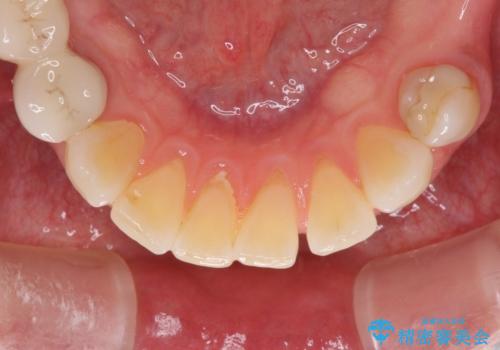

- 口の中に気になるところが沢山あるものの、地元ではなかなか治療を行ってくれるところがないとのことで、沖縄県の離島より来院された患者様です。

金属を使用した前歯のブリッジや奥歯の銀歯は全てオールセラミッククラウンまたはセラミックインレーとし、左下の奥歯はインプラントにより治療を行うこととしました。

外科処置を行うため、治癒を待つ期間が数ヶ月あるため、その期間を利用して下顎前歯のスペースを矯正治療で閉じることとしました。